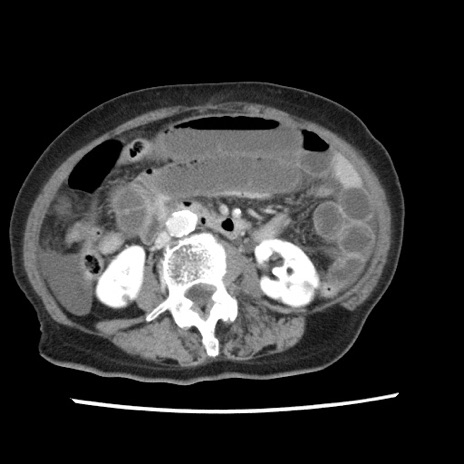

【症例】80歳代女性

【主訴】腹痛

【現病歴】8時間前から腹痛あり来院。

【既往歴】糖尿病、脂質異常症、子宮体癌にて子宮全摘術

【身体所見】意識清明・会話良好だが腹痛で苦悶様、全腹部にわたって反跳痛と圧痛あり

【データ】WBC 13600、CRP 0.14、LDH 224、CK 90